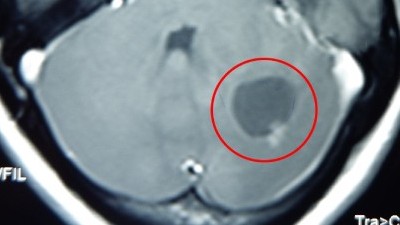

Dấu hiệu khối u đang phát triển trong phổi

Bệnh ung thư -  11/04/2021

Nguyên nhân dẫn tới ung thư trong phổi có thể do hít phải khói thuốc lá - trực tiếp hoặc thụ động. Tỷ lệ sống tùy thuộc vào độ lớn của khối u và liệu...